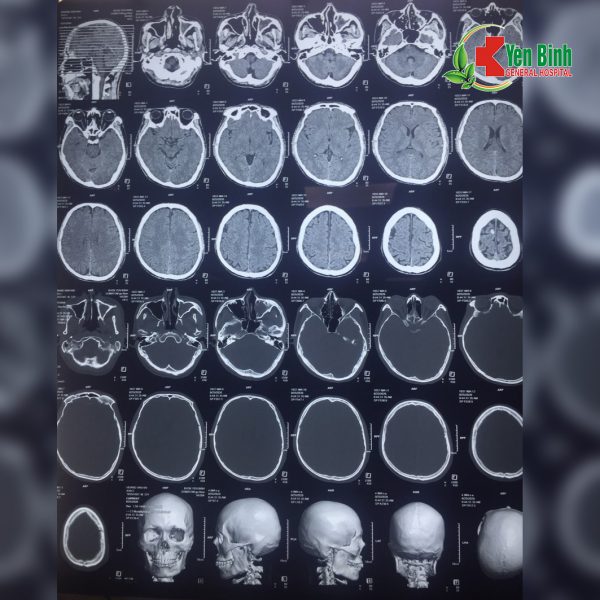

Hình ảnh chụp CT sọ não của bệnh nhân Hoàng Văn.H (Hình ảnh do bác sỹ Bệnh viện Đa khoa Yên Bình cung cấp)